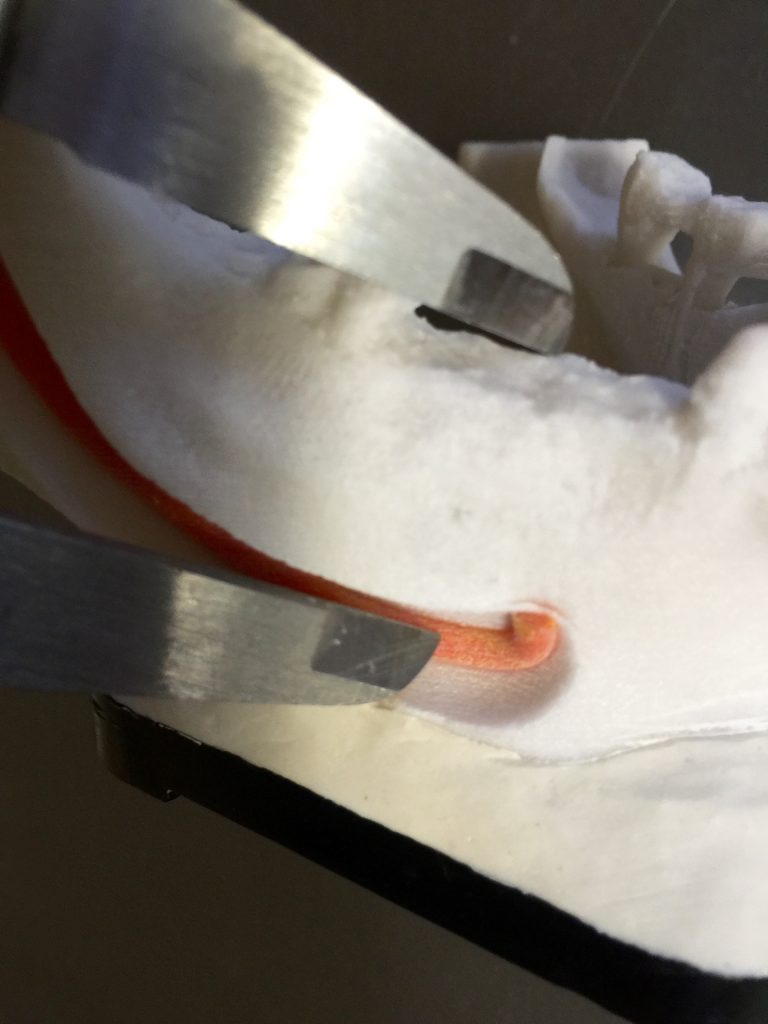

FIG: 21-22-23-24-25-26

Fig. 21

Fig. 22

Fig. 23

Fig. 24

Fig. 25

Fig. 26